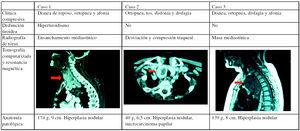

Se diagnosticó de hipotiroidismo secundario a la toma de antitiroideos, que mejoró tras la instauración de tratamiento con levotiroxina. Una vez desaparecido el cuadro mixedematoso, la insuficiencia respiratoria se mantuvo, asociada con ortopnea muy marcada, por lo que se realizó una prueba de imagen con tomografía computarizada (TC), que mostró un bocio grande que se introducía en el opérculo torácico hasta troncos supraaórticos, que producía compresión de la tráquea con disminución de su diámetro transversal (fig. 1). Se trató quirúrgicamente resecándose la masa por cervicotomía. El paciente mejoró notablemente, y desapareció la sintomatología respiratoria. Un año después el paciente se mantenía asintomático.

Figura 1. Características clínicas, radiológicas y patológicas.

A la exploración estaba consciente, poco colaboradora y bradilálica. Presentaba palidez cutánea, presión arterial de 125/70 mmHg, frecuencia cardíaca de 60 lat/min y tiroides no palpable. A la auscultación se evidenció la presencia de crepitantes basales en ambos hemitórax. Tenía edemas con fóvea en miembros inferiores y hemiparesia izquierda. En la TC (fig. 1) se observó un BET en el mediastino superior que desplazaba la vía aérea.

En las pruebas de imagen (fig. 1) se observó una masa de 9 cm de diámetro en el mediastino inferior. El estudio gammagráfico con tecnecio-99 de la glándula tiroidea mostró una masa mediastínica captante del isótopo. Se la intervino por cervicotomía sin complicaciones postoperatorias. La paciente experimentó una notable mejoría tras la intervención.